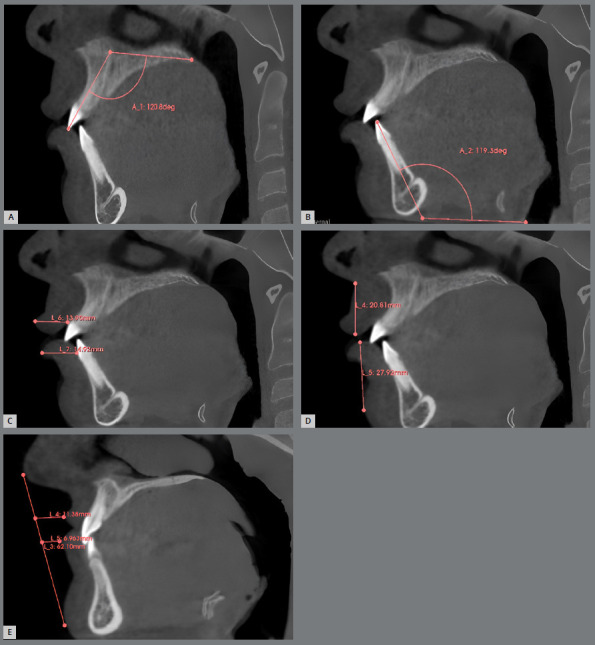

Objective: This study seeks to explore the correlation between incisors inclination and various lip parameters utilizing CBCT technology. Moreover, it aims to assess whether specific incisors inclinations significantly influence lip thickness, length, and position.

Material and methods: This was a retrospective observational study of available records of orthodontic patients (n=84) aged between 11 and 17.5 years old with pre- and post-treatment CBCT imaging. The 3D Slicer software was used to assess lip parameters and incisors inclinations while adhering to standard CBCT imaging methods. Statistical analysis was conducted to find associations between incisors inclination and lip parameters.